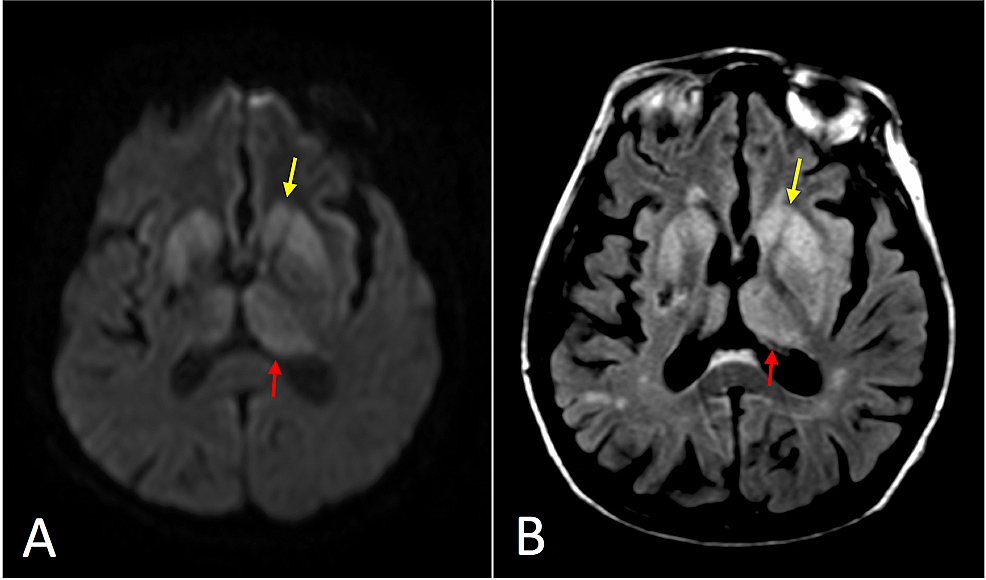

Case 4, a 36yearold man with CreutzfeldtJakob disease. A Creutzfeldt-Jakob Disease Cases Per Year Cjd occurs worldwide with an estimated rate of about one to two illness per one million population members per year. A) total number of reported cases per year and sex. Creutzfeldt-Jakob Disease Cases Per Year.